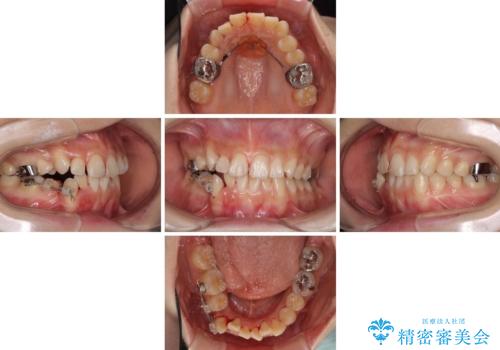

- 上下の八重歯を気にして来院された患者様です。

上下ともに八重歯の後ろの歯を1歯ずつ抜歯し、補助装置(リンガルアーチ)を用いて八重歯の位置を改善し、その後インビザラインにより矯正治療を行うこととしました。

途中海外留学をされたため、治療期間は長くなりましたが、事前に補助装置やワイヤー装置を併用したことで、きれいな歯列に仕上げることができました。